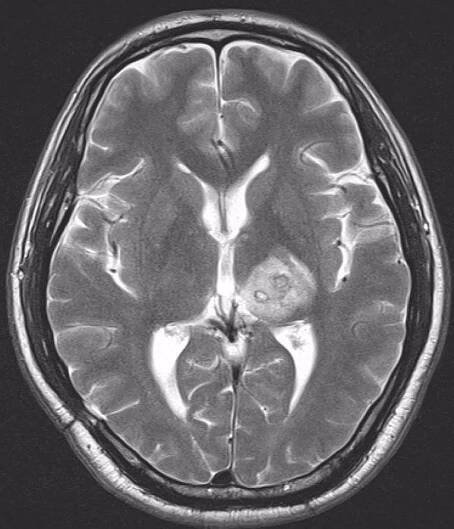

Mozkové metastázy je nádorové onemocnění, kdy nádor vznikne v jiné části těla a do mozku se následně rozšíří. Někdy se tento tumor nazývá sekundární. Jedná se…

Nádor mozku, někdy též nesprávně označovaný jako rakovina mozku, je ročně diagnostikován přibližně 700 – 800 pacientům v České republice. Představuje asi 1,5 % ze všech zhoubných nádorových onemocnění.